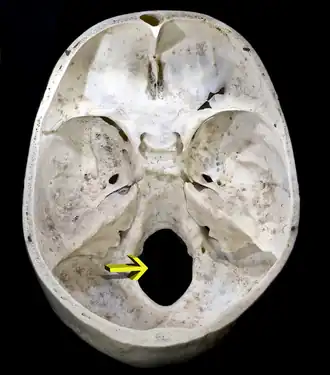

![]() Superficie interior de la base del cráneo. El agujero señalado por la flecha es el foramen magno. | ||

Foramen magnum, también conocido como agujero magno o agujero occipital, es el nombre del orificio mayor situado en la parte posteroinferior del cráneo (base del cráneo, piso témporo occipital), a través del cual se establece la continuidad del sistema nervioso central hacia el raquis.

Por el agujero magno van a pasar: el bulbo raquídeo, sus meninges, las arterias vertebrales y sus ramos meníngeos, y también los nervios espinales.